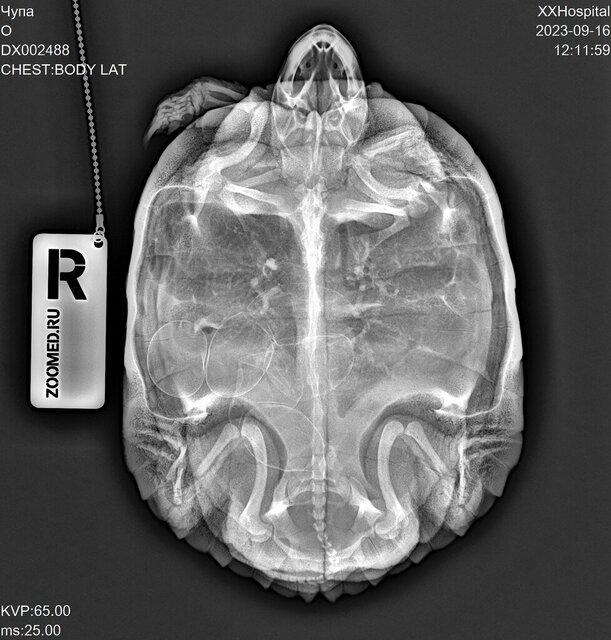

Abc01 Ваше имя: Арина Локация: Россия, Спб Опубликовано: 16 сентября 2023 Опубликовано: 16 сентября 2023 1. Сочи, 22 года. 2. Красноухая черепаха, самка. 3. 50-литровый контейнер, пока нет возможности из-за ремонта купить 100-литровый. 4. Фильтр, уф-лампа (не греющая, просто уф-лампа), термометр. 4.1. Нет лампы накаливания, должна 20 сентября прийти с озона лампа Sera Reptil Sun Heat 100Вт, она и с УФ и греющая, но производитель не пишет, какой именно процент UVB. На сайте черепахи.ру она была в списке рекомендованных, поэтому ее заказала. 4.2. На данным момент стоит только уф-лампа RESUN UVB-10%, стоит с 2 мая, включаю с 9 до 23. 4.3. В качестве берега использую камень, большой, больше 7 кг, черепаха взбирается на него и лежит на нем всем телом под лампой. 4.4. Установлен фильтр внутренний AQUAEL FAN FILTER 1 plus для аквариума 60-100л (320л/ч, 4.7Вт) 4.5. На данный момент обогревателя нет, так как весной вышел из строя и его пришлось выкинуть. Грунта нет. Термометр показывает температуру воды 26 градусов. Температура в комнате такая же, если не выше. Черепаха ест Tetra ReptoMin Sticks, до случившегося ела понемногу каждое утро. Последние 1,5-2 недели давала примерно каждые 3 дня чайную ложку фарша минтая с витаминной добавкой "АВЗ Рептилайф витаминно-минеральная добавка для рептилий, 30 гр" и порошком "Минеральный MIX с кальцием". Как сказал сегодня вет.врач, черепахе примерно 10 лет, вес 1,385 кг. Примерно 3 недели назад черепаха начала очень суетно себя вести, норовила вылезти из контейнера. Уже три недели ходит по комнате и "роет ямки", сначала передними лапками, потом поочерёдно правой и левой задними лапками, потом переползает на другое место и так по новой, целыми днями. Сегодня пошли к ветеринару, сделали рентген. По рентгену 6 яиц, фото прилагаю. Ветеринар сказала, что у черепахи рахит, что очевидно по искривлению на панцире. Мне ее такой отдали в 2020 году, она была уже взрослая и с кривым панцирем. Ветеринар сказал, что панцирь уже не выпрямится никакими препаратами. Также ветеринар сказала, что таз у черепахи узкий, что яйца при откладке могут застрять и черепаха не сможет разродиться. Ветеринар сказала, что, возможно, придется делать операцию. Рекомендация была дать ей попробовать разродиться самой, дать ей дальше перемещаться и искать себе место, но быть готовой к операции и поискать ветеринара, который успешно сможет ее провести. Ветеринар сказала, что не стоит стимулировать черепаху к кладке. Также ветеринар сказала, что пока нужно перестать давать кальций, так как яйца могут закальцинироваться. До приема у врача предлагала черепахе садок с землей, садок с опилками, но они ей не нравились и она из них вылезала. Она часто роет на линолеуме или коврике для фитнеса. Сегодня принесут песок, предложу ей садок с песком, предварительно помыв его. Очень хочу узнать мнение профессионалов по поводу рентгеновских снимков и, если можно, наводку на хорошего в этом вопросе врача, который проводит онлайн-консультации. Также хочу узнать ваше мнение, можно ли как-то еще помочь черепахе разродиться, кроме предложение субстрата? Я нахожусь в Сочи и мне бы хотелось узнать, есть ли у нас специалисты (хотя бы в краснодарском крае), которые могли бы провести эту операцию, в случае, если она будет нужна? Обращались вет.клинику Айболит, врач Аносова Мария Александровна. Никаких препаратов не вводилось.

Консультанты moth Ваше имя: Мария Локация: Москва Опубликовано: 17 сентября 2023 Консультанты Опубликовано: 17 сентября 2023 @Abc01 наш герпетолог ответила, что черепаха должна разродиться сама - яйца стоят хорошо, вопрос только в "замятышах" (яйца неправильной формы), но и они должны нормально выйти, если черепаха активная. Я ей задала ещё пару уточняющих вопросов про стимуляцию и сколько вообще можно ждать - напишу как ответит. 1

Abc01 Ваше имя: Арина Локация: Россия, Спб Опубликовано: 2 ноября 2023 Автор Опубликовано: 2 ноября 2023 Не знаю, может, эта хроника по поводу действий над черепахой на сносях будет кому-то интересна. Связалась с Татьяной из Беларуси, получила консультацию. Она сказала, что кальций нужно давать, так как яйца все равно будут кальцинироваться, просто черепаха будет черпать этот кальций не из еды, а из своего организма, грубо говоря, из своих костей. Татьяна заметила, что по рентгену не видит рахит, что кости хорошей контрастности. Т.е. в детстве он был, если судить из кривизны панциря, но сейчас все с кальцием хорошо. Назначили бороглюканат кальция после второго рентгена (рентген не был пока сделан, кальций еще не был принят на данный момент). Показала фото, как колоть. Сказала снизить температуру с 26 на 24 градуса, чтобы черепаший гормональный фон снизился, а то она так потенциально может постоянно культивировать в себе яйца, думая, что все условия для этого есть (типа тепло, хорошо, самое время сносить яйца). Уже второй специалист подтвердил, что она должна сама снестись, что никаких физиологических проблем не должно быть. Консультация была 9 октября. Татьяна сказала, что выглядеть все будет следующим образом: вода в садке станет белесой, мутной, что на это нужно обратить внимание, так как это будет признаком кладки, яйца черепаха может моментально съесть после этого. По хронике: спустя несколько дней после консультации поставила новую лампу Sera Reptil Sun Heat 100Вт. Чупа стала с огромным удовольствием под ней греться, буквально не сходила с камня-островка. Лампа помимо УФ-излучения еще и греющая. Пока не было денежной возможности сделать рентген, а пока не сделан рентген нельзя стимулировать кальцием, поэтому единственным изменением стало появление новой УФ-лампы с греющей функцией. 28 октября я проснулась и увидела перед собой активную Чупу, плавающую в мутной белесой воде, были видны какие-то белые кусочки. Я вспомнила, что воду меняла вчера, что фильтр работает, и что меня должна была встретить Чупа в чистой водичке и никак иначе. Сразу подлетела с кровати к садку. Все в точности, как описывала врач. На момент находки в садке были уже множество фрагментов скорлупы и кусочков яиц. Лишь одно уцелело, уплыв за камень-островок. Яйца и правда с мягкой скорлупой. Очень довольна. С зарплаты пойду делать рентген, чтобы посмотреть, что осталось или, не дай бог, прибавилось. Единственное, не знаю, как технически сделать температуру воды в садке ниже. Яйцо Это какое-то из замятых яиц, которое видно на рентгене, не смогла понять, какое именно.